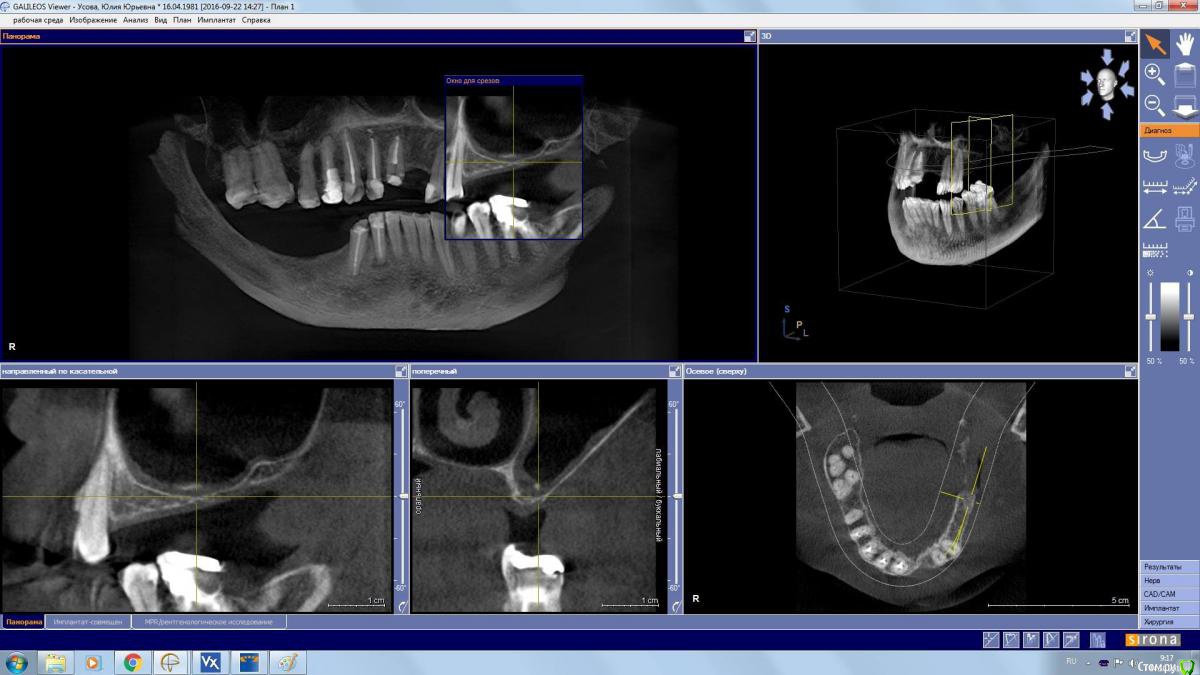

kamranchick Опубликовано 22 октября, 2016 Поделиться Опубликовано 22 октября, 2016 Сегодня сделал первый в жизни открытый синус 2 часа ушло на все про все) 1 Ссылка на комментарий

АнтонТЛТ Опубликовано 22 октября, 2016 Поделиться Опубликовано 22 октября, 2016 Камран, мало поднял 1 Ссылка на комментарий

kamranchick Опубликовано 22 октября, 2016 Поделиться Опубликовано 22 октября, 2016 Камран, мало поднялБоялся если честно, и до какого уровня надо было поднимать....Проблема в том, что как от небной стенки отслаивать пазуху? Ссылка на комментарий

kamranchick Опубликовано 23 октября, 2016 Поделиться Опубликовано 23 октября, 2016 Перед имплантацией сделайте КТ. Если до нёбной не дошли материалом, могут быть сложности. А в остальном - до 26 поставите от 2 до 3 шт (даже если даст усадку)Обязательно. Планирую через 7 месяцев сделать Кт Спасибо Ссылка на комментарий

kamranchick Опубликовано 24 октября, 2016 Поделиться Опубликовано 24 октября, 2016 А как отслаиваться от небной стенки? есть книги?В атласе Коэна очень кратно описано...Антон описал чем отслаивать, спасибо ему за это.если быть точнее то как? Ссылка на комментарий

АнтонТЛТ Опубликовано 24 октября, 2016 Поделиться Опубликовано 24 октября, 2016 http://i85.fastpic.ru/big/2016/1024/0e/9816346eac32b33880663f66e99b2b0e.jpg 9 Ссылка на комментарий